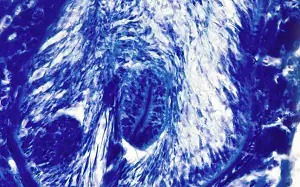

Diagnosis of Mesocestoides sp. is based on the morphological identification of proglottids in the stool. While gravid proglottids have a characteristic morphology, immature proglottids may be difficult to differentiate from those of Diphyllobothriidae. Accurate identification of species is complicated and requires complete specimens.